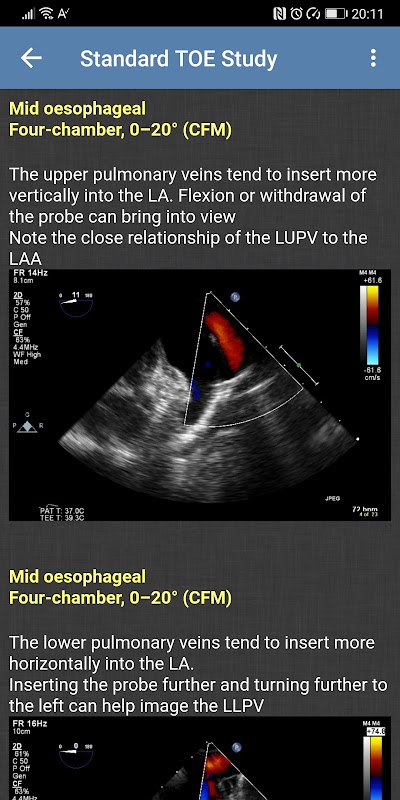

- স্ট্যান্ডার্ড টোই স্টাডি